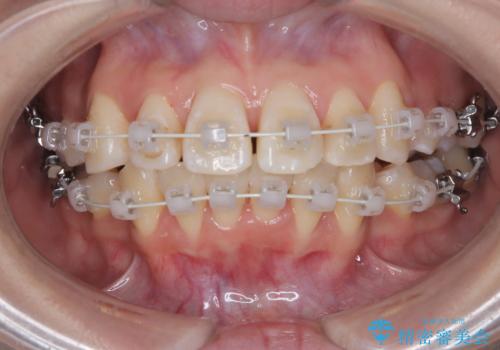

今回の矯正治療では、まず計画通り上下左右の小臼歯4本を抜歯し、八重歯や正中のズレを解消するための十分なスペースを確保しました。装置には、目立ちにくい白いブラケットとワイヤーを使用した審美ワイヤー矯正を採用。

抜歯によってできたスペースを利用し、

八重歯: 突出していた八重歯を歯列内に誘導し、デコボコを解消しました。

正中のズレ: 歯を左右対称に移動させることで、上下の歯の中心線を正確に合わせ、顔全体のバランスも改善しました。